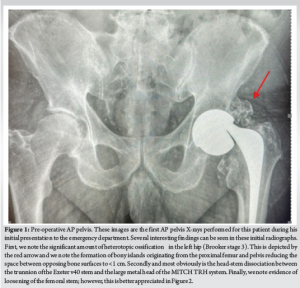

The surgical wound was closed in layers in a standard fashion with PDS sutures and skin clips. Following a confirmation of negative tissue samples and cultures swabs from the microbiology laboratories, opinion was sought from the infectious diseases team regarding 2nd stage revision. Given that the patient had negative culture swabs and pre-operative inflammatory markers were normal, decision was made to proceed with early 2nd stage revision 1 week after the 1st stage procedure. The same surgical incision was used to regain access to the hip joint. The cement spacer was removed and the final components (cemented Exeter v40 stem size 1 with 50 mm offset, 36 mm standard ceramic head, 58 mm Trident Hemispherical Uncemented cup with 36 mm 10° eccentric insert) were implanted (Fig. 6). The hip was stable in all ranges of motion, and leg lengths were equal. The surgical wound was closed again in a similar fashion to the 1st stage procedure with PDS sutures and skin clips.